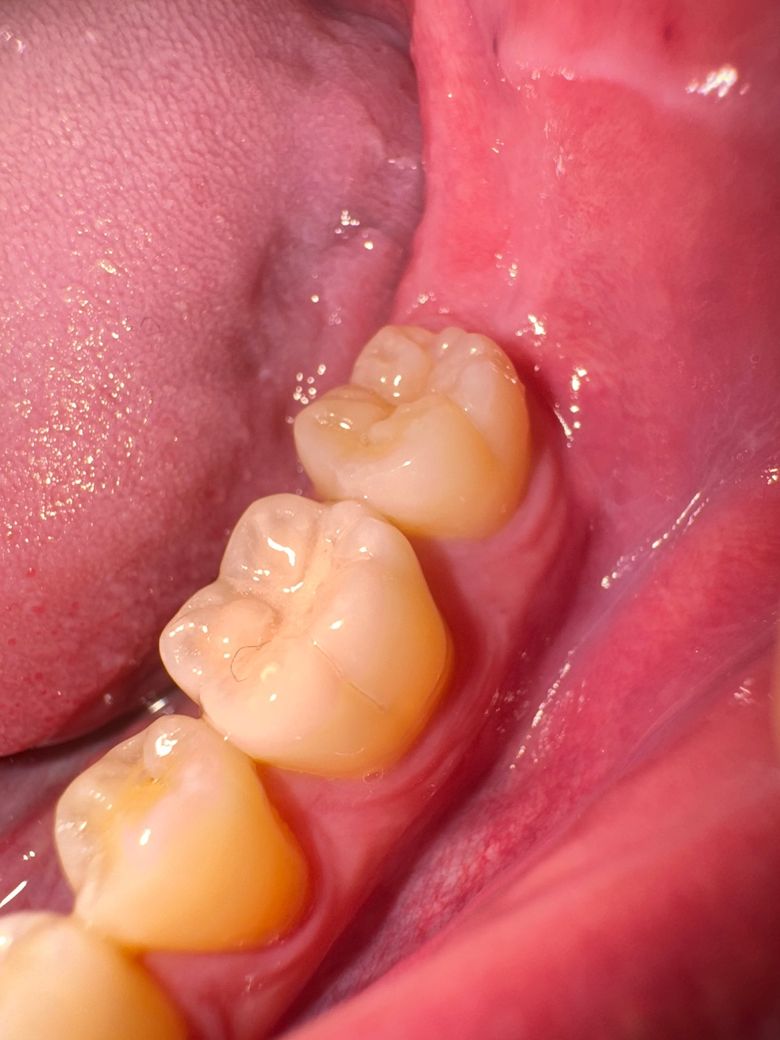

어금니 크랙... ㅜㅜㅜㅜㅜㅜㅜㅜ

이거 크랙 맞나요. 특별한 증상은 없지만 라인이 너무 선명해서요 ㅜㅜㅜㅜㅜㅜㅜㅜㅜㅜㅜㅜㅜㅜㅜㅜㅜㅜㅜㅜㅜㅜㅜㅜㅜㅜㅜㅜ

사진에 보이는건 크랙라인은 아닌거 같습니다. 치아 바깥쪽에 잇는 치아의 정상적인 구조입니다.

사진으로는 정확한 확인이 어려워 보입니다. 단순히 크랙이라기보다 충치 등이 생겨 있을 가능성이 있어 보입니다.

자세한 확인을 위해서 치과에서 진료를 받아보는 것을 권유드립니다.

두가지 가능성이 있습니다. 크랙일 수도 있고, 원래 존재하는 해부학적 구조일 수도 있습니다. 치과가서 바이트테스트 해보세요. 씹을때 아프거나 찬물에 시리면 크랙일 가능성이 좀 더 높습니다